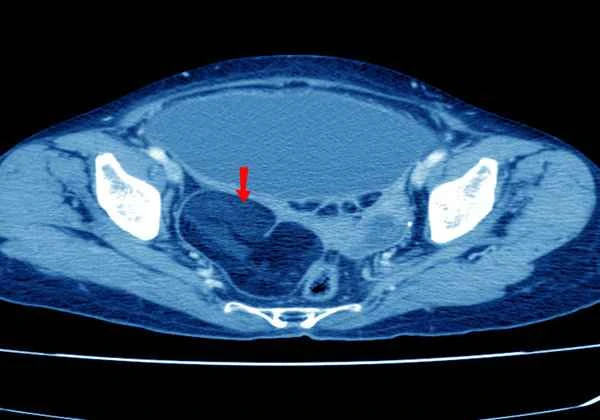

The diagnosis of advanced gastric cancer is typically based on the results of endoscopy, imaging studies, and pathological examination. Endoscopy allows for direct visualization of the morphology and location of tumors within the stomach, and also allows for biopsies to be taken for pathological analysis. Imaging studies such as CT and MRI help doctors understand the size and location of the tumor, as well as whether there are distant metastases. These examinations, taken together, provide doctors with comprehensive information about the patient's condition, enabling them to develop more precise treatment plans.